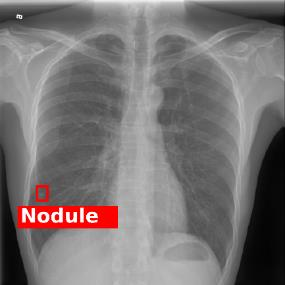

Chest X-ray (CXR) is the most typical diagnostic X-ray examination for screening various thoracic diseases. Automatically localizing lesions from CXR is promising for alleviating radiologists' reading burden. However, CXR datasets are often with massive image-level annotations and scarce lesion-level annotations, and more often, without annotations. Thus far, unifying different supervision granularities to develop thoracic disease detection algorithms has not been comprehensively addressed. In this paper, we present OXnet, the first deep omni-supervised thoracic disease detection network to our best knowledge that uses as much available supervision as possible for CXR diagnosis. We first introduce supervised learning via a one-stage detection model. Then, we inject a global classification head to the detection model and propose dual attention alignment to guide the global gradient to the local detection branch, which enables learning lesion detection from image-level annotations. We also impose intra-class compactness and inter-class separability with global prototype alignment to further enhance the global information learning. Moreover, we leverage a soft focal loss to distill the soft pseudo-labels of unlabeled data generated by a teacher model. Extensive experiments on a large-scale chest X-ray dataset show the proposed OXnet outperforms competitive methods with significant margins. Further, we investigate omni-supervision under various annotation granularities and corroborate OXnet is a promising choice to mitigate the plight of annotation shortage for medical image diagnosis.